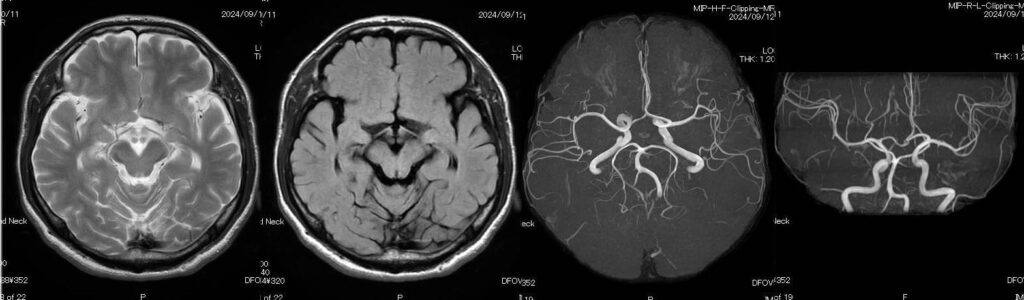

MRIは、脳や血管、内臓、筋肉などの状態を詳細に確認することができます。特に以下のような疾患の早期発見に役立つとされています。

・脳梗塞の前兆となる小さな脳血管の変化

・脳腫瘍

・脳動脈瘤

また、人間ドックでは脳ドックとしてMRIを利用するケースが多く、自覚症状が出る前の異常を見つけることが可能です。